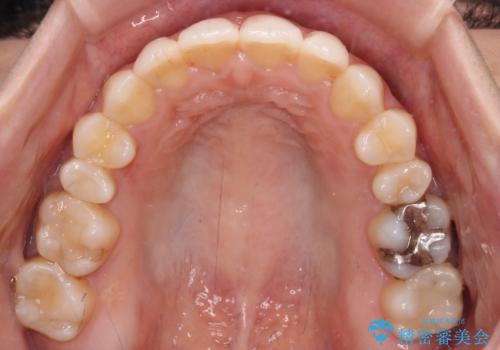

- オープンバイトのため、話しているときの見た目が気になるとのことで来院された患者様です。

下顎骨は左側にシフトしており、咬み合ったときには奥歯と前歯の一部しか接触していない状態でした。

骨格的な左右差は歯列矯正は改善できないため、上下歯列が全体的に接触することをゴールとしてインビザラインにて矯正治療を行うこととしました。

前歯のデコボコの解消と並行して上下の奥歯を圧下させるようにすることで、前歯を接触させるように計画しました。